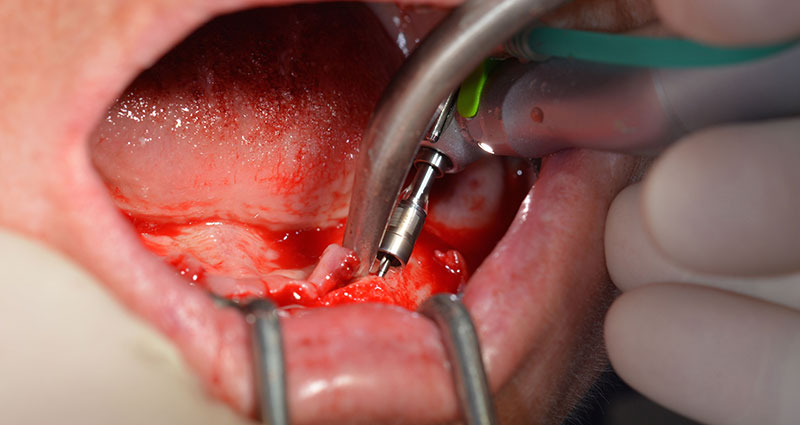

Le trou mentonnier doit d'abord être identifié comme une structure anatomique limitante, puis l'os cortical de la crête a été régularisé avec une pièce à main droite et une fraise sphérique de grande taille (Fig. 4).